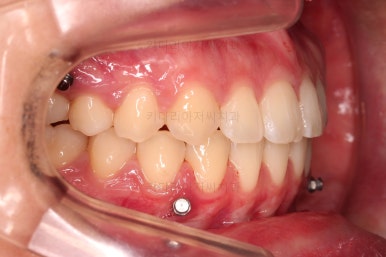

그래서 위아래 좌우 모두 다른 용도로 미니스크류가 식립되었고요.

아랫니 틈은 거의 없어졌네요.

대신 여러 교합적인 이유로 아랫니를 좀 더 앞으로 당겨주긴 해야 합니다.

이제 마무리를 해봅니다.

교합 양호하고 치아 사이 틈새도 잘 모아졌습니다.

이제 부산치아교정 전후 비교를 해볼게요.

틈새가 예쁘게 모아졌고요.

교합도 좋아졌고, 앞니도 가지런해졌네요.

당연히 얼굴 모습도 마이너스 없이 예쁘게 마무리가 잘 되었습니다.

이상 미니스크류를 이용해 어금니를 전방으로 당겨오면서 틈새를 모아주었던 부산치아교정 치료사례였습니다.